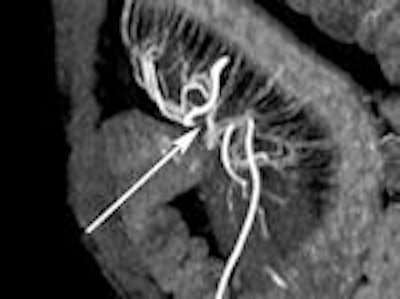

Patient with active ileocolonic Crohn's disease.

Small-bowel imaging guides therapeutic management of Crohn's disease by informing the clinician about the location, extent, and activity of pathology, according to Dr. Sam Stuart, a radiologist with Royal Free Hospital in London. Imaging aids diagnosis, monitors progression, assists treatment, and identifies small-bowel strictures that may need surgical resection.

CT enterography (CTE) has largely replaced small-bowel follow-through as the imaging modality of choice for Crohn's disease. Its popularity stems from its ability to noninvasively investigate extraintestinal effects of inflammatory small-bowel disease located outside the reach of x-ray barium imaging.